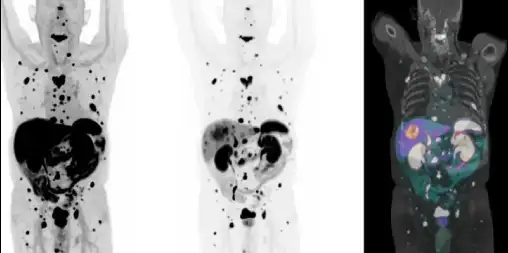

PSMA PET-CT

Prostate cancer • Ga-68 PSMA (Illucix™) • F-18 PSMA (Pylarify™ or Posluma™)

PSMA PET targets prostate-specific membrane antigen, overexpressed by prostate cancer cells and metastases.